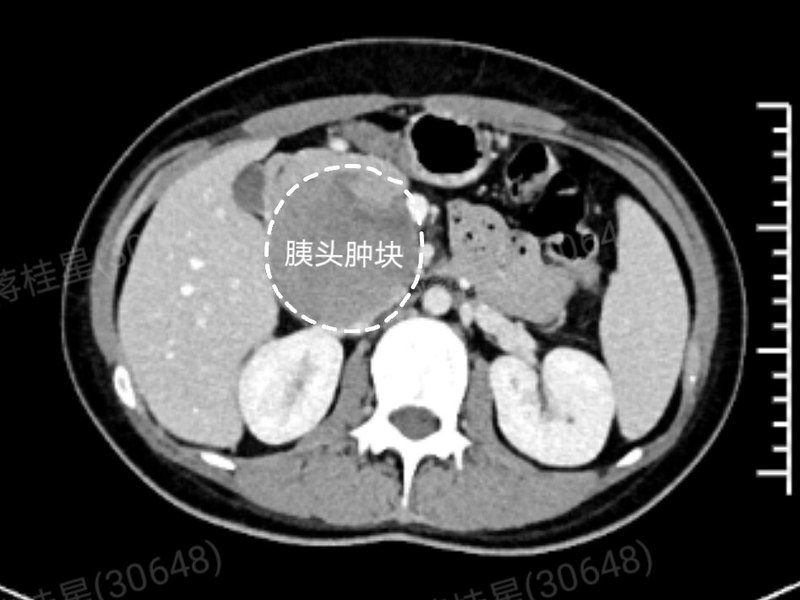

1例20歲的女大學(xué)生,體檢發(fā)現(xiàn)胰腺頭部巨大腫塊,按常規(guī)需要行胰十二指腸切除(切除胰頭,部分胃,膽囊膽管,十二指腸,部分空腸等器官),考慮到年紀(jì)這么輕又是良性腫塊,盡量在切除腫塊的同時(shí)保留更多器官和功能,盡量減少對(duì)小姑娘的創(chuàng)傷,遂做了腹腔鏡下胰頭腫塊剜除,保留了原本需要切除的胰頭,部分胃,膽囊膽管,十二指腸,部分空腸等器官,術(shù)后恢復(fù)也很順利,這個(gè)手術(shù)雖然縮小了切除范圍,但大大增加了手術(shù)難度,需要更精細(xì)化,更精準(zhǔn)的操作。